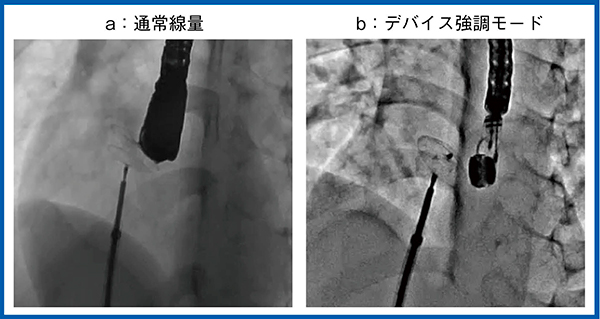

小児循環器領域においては,小児の細い血管に対して冠動脈ステントを留置する機会が増えているため,デバイスの視認性も重要となる。しかし,従来システムでは低線量の透視において,ステントなどの各種デバイスを視認しづらい場合も多かった。Alphenixシリーズでは,新しい画像処理を搭載したデバイス強調モードにてステントやガイドワイヤを明瞭に描出できるようになっている(図1)。

図1 デバイス強調モード:経皮的冠動脈形成術